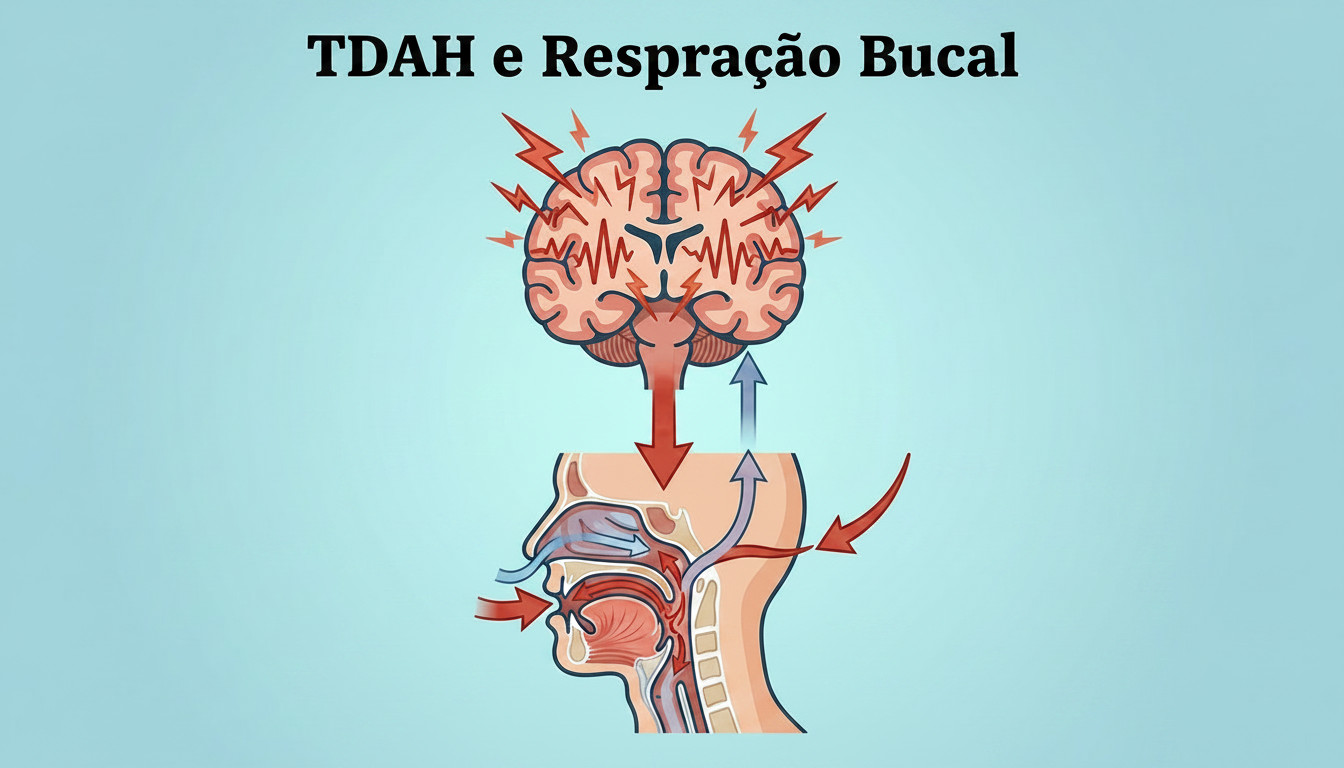

Para compreender melhor sobre os efeitos da compressão maxilar acesse nosso infográfico sobre respiração bucal e desenvolvimento das arcadas dentárias.